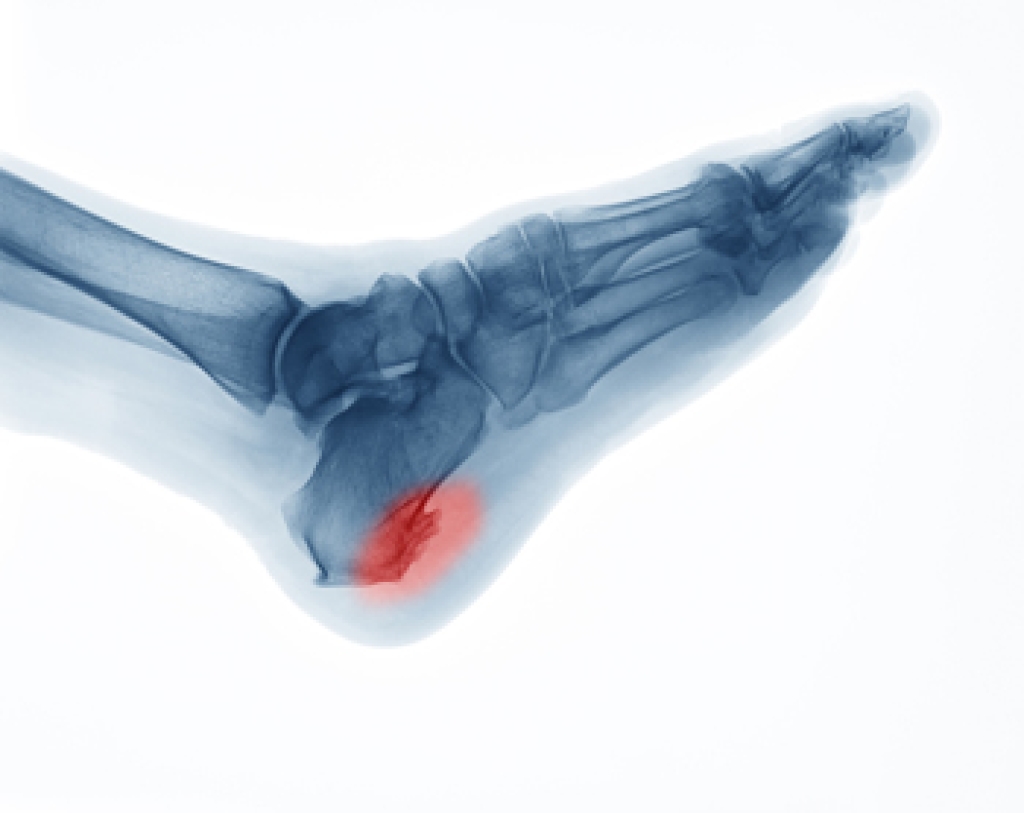

Heel spurs are a bony growth that can develop on the underside of the heel bone, pointing towards the toes. Like many foot conditions, pain is a symptom linked to heel spurs. However, not all patients with heel spurs feel pain. Interestingly, only a fraction of those living with heel spurs experience pain. Often, heel spurs may be associated with plantar fasciitis, in which case pain can be felt at the bottom of the foot. Pain from heel spurs and plantar fasciitis can be more pronounced in the morning. If you are living with heel spurs, then it is suggested that you schedule an appointment with a podiatrist who can help you treat your condition.

Heel spurs are formed by calcium deposits on the back of the foot where the heel is. This can also be caused by small fragments of bone breaking off one section of the foot, attaching onto the back of the foot. Heel spurs can also be bone growth on the back of the foot and may grow in the direction of the arch of the foot.

The pain associated with spurs is often because of weight placed on the feet. When someone is walking, their entire weight is concentrated on the feet. Bone spurs then have the tendency to affect other bones and tissues around the foot. As the pain continues, the feet will become tender and sensitive over time.